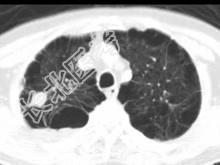

- 单项选择题男,76岁, 气喘数年,胸痛一月余, 结合影像图像,选择最可能的诊断 ( )

A、右上肺结核球

B、肺间质纤维化

C、右上肺瘢痕癌

D、右上肺错构瘤

E、右上肺肉瘤